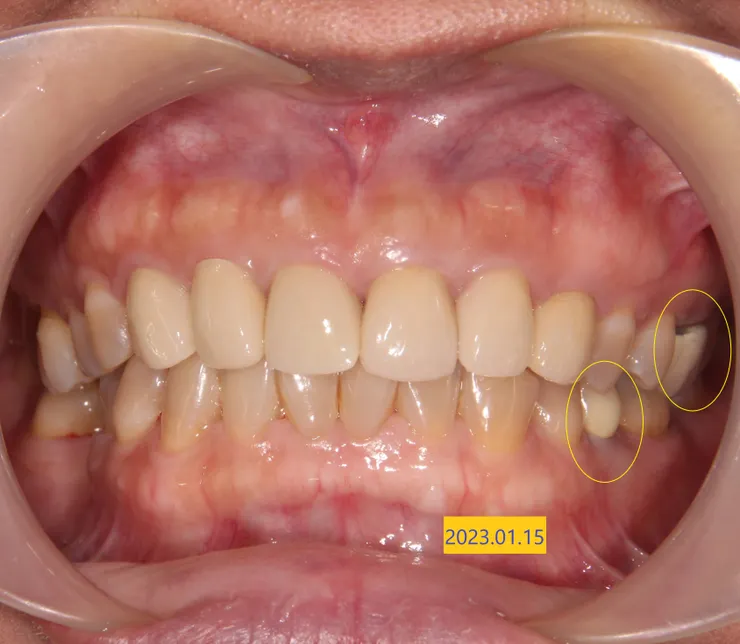

這位病人來的主訴(主要的訴求、想解決的問題),是想想換掉剛做2年的上前牙假牙。因為瓷裂,已補過多次。左上牙齦有時會壓痛,假牙內有時會塞東西,會臭臭的。目前在台灣這種假牙還是主流,金屬瓷牙(PFM),牆國用語是烤瓷牙。

原來連在一起的假牙,以修飾成人牙齦萎縮的問題,下詳內文另外也請注意6顆假牙邊緣的牙齦,全都有程度不一的暗紫紅色慢性發炎,尤其瓷裂處,看下圖拆完假牙的圖,才知造成發炎的真相,難怪病人說有時刷牙會流血

臨床我看,其實還好,病人上嘴唇在一般時候,是會蓋住瓷裂的地方,除非大笑之類的,旁人其實不會覺得那個假牙是有瑕疵的。我的意思是說,沒急迫性。但病人會故意拉開,堅持要處理,即使2年前才花幾萬塊做了這6顆假牙。